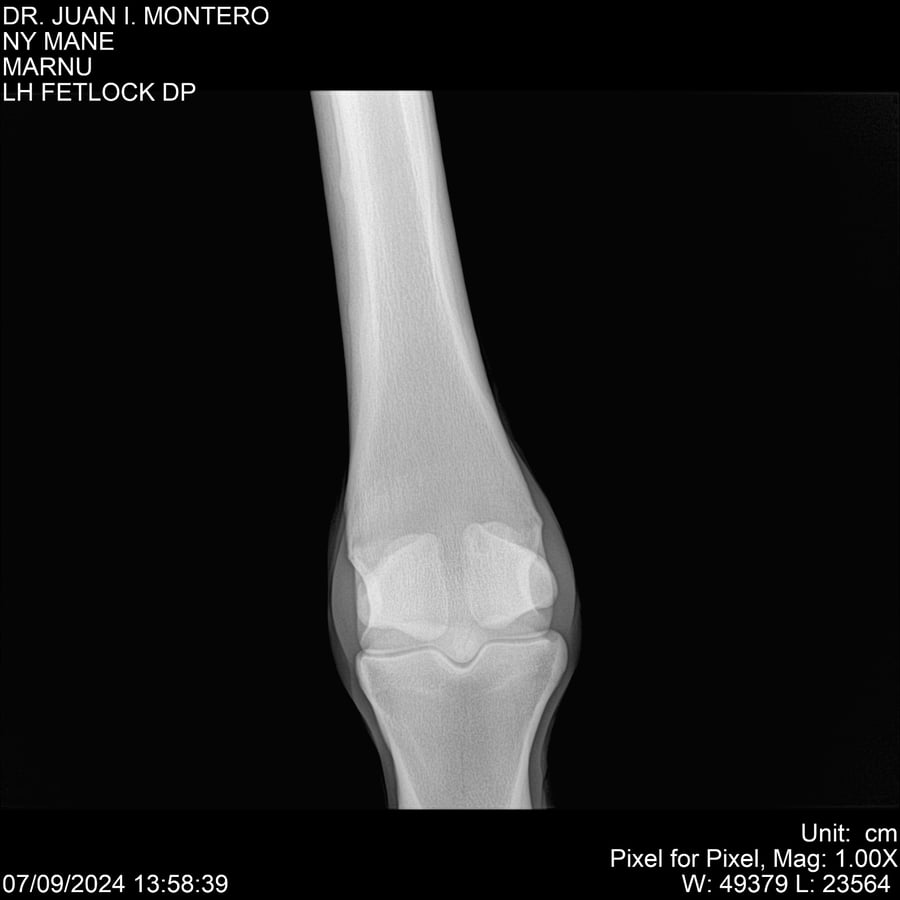

LOTE 20, NY MANE Lote Anterior Volver al remate Lote Siguiente Ficha Contacto Montevideo - Ficha del Lote Identificador: #282520 Categoría: Yeguarizos 76 Visualizaciones ClicData Contacto Empresa: Abelenda N. R., Walter Hugo Nombre*: Teléfono* : E-mail* : Mensaje Enviar Registrese gratis Este contenido Exclusivo está disponible sólo para usuarios registrados Ingresar